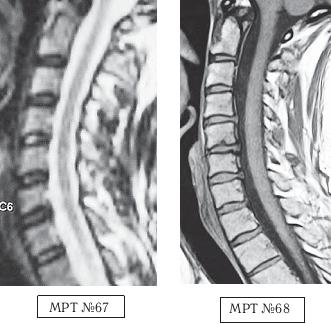

МРТ № 2

На МРТ № 2 — грудной отдел в состоянии «норма»

Грудной отдел должен иметь нормальную степень кифоза (угол кифоза по Stagnara формируется линией, параллельной замыкательным пластинкам ТIII и ТXI= 25°). Позвоночный канал на грудном уровне имеет округлую форму, что делает эпидуральное пространство узким почти по всей окружности дурального мешка (0,2–0,4 см), а на участке между TVI и ТIX он наиболее узок. Сагиттальный размер: ТIХI = 13–14 мм, ТXII = 15 мм. Поперечный диаметр: > 20–21 мм.

Высота межпозвонковых дисков: самая меньшая на уровне ТI, на уровне ТVIХI приблизительно 4–5 мм, наибольшая на уровне ТХIХII.